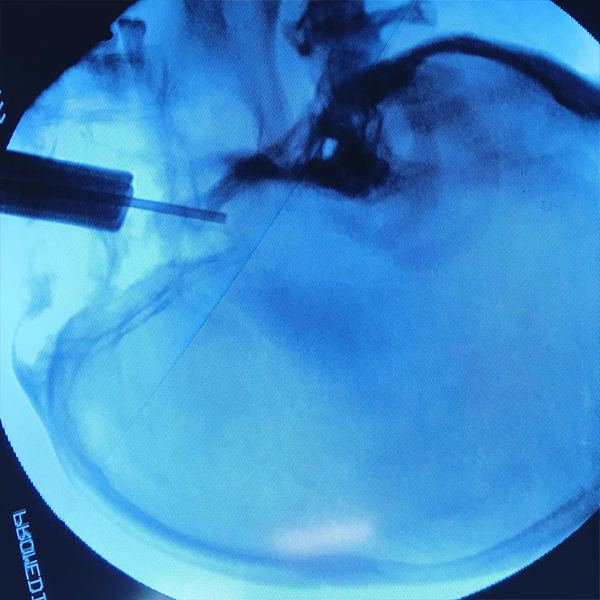

Cirugías de columna

La cirugía de columna permite descomprimir, movilizar los elementos, fijar estructuras vertebrales y sustituirlos. La cirugía de la espalda es una opción a tener en cuenta en el momento en el que tratamientos conservadores no han funcionado y el dolor sigue siendo persistente e impide el desarrollo de una vida normal. Existen diversos tipos de cirugía de espalda:

Cirugía de la columna

lumbar

cervical

torácica

Estoy a sus órdenes para brindarle la mejor atención médica, con gran calidez humana y la mayor experiencia para resolver su padecimiento con el uso de técnicas modernas, seguras y de mínima invasión.